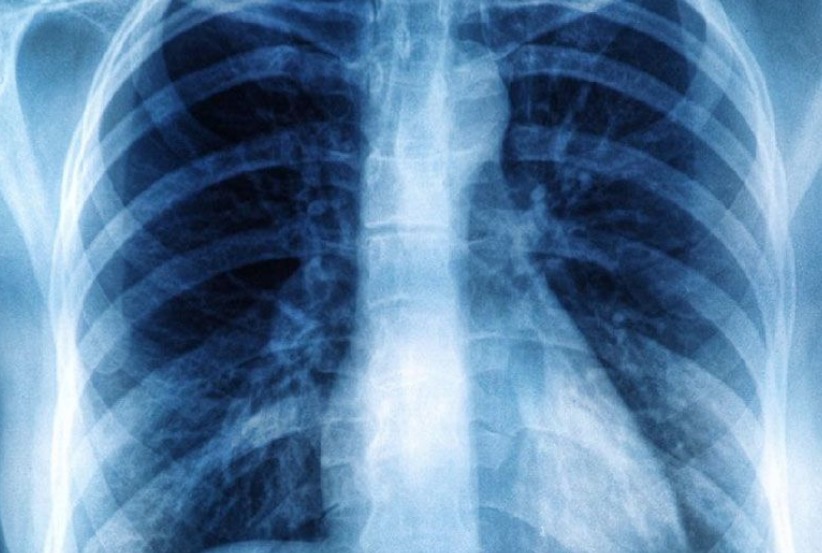

Uma campanha da Sociedade Brasileira de Pediatria (SBP) alerta para os riscos da exposição excessiva de crianças e adolescentes a exames de diagnóstico por imagem como tomografias computadorizadas e raios x.

“Para os médicos, os exames de imagem (raios x, tomografias, ultrassonografias e ressonância) são muito úteis à medicina e, por vezes, essenciais ao diagnóstico em adultos e crianças. Entretanto, alguns desses exames emitem radiação nociva à saúde e, por isso, a SBP, em parceria com outras entidades nacionais e internacionais, lança uma campanha que alerta sobre o uso racional dessas ferramentas. Além dos pediatras, os radiologistas e outros técnicos envolvidos no processo também devem ser bem orientados”, explicou a entidade, por meio de comunicado.

Para a presidente da SBP, Luciana Rodrigues Silva, é preciso cautela para não expor crianças e adolescentes a riscos desnecessários. Essa população, segundo ela, possui tecidos e órgãos ainda em desenvolvimento e apresenta, portanto, maior sensibilidade aos efeitos da radiação ionizante sobre o corpo humano. Quanto mais jovem for o paciente, maiores são as chances de desdobramentos adversos.

Ainda de acordo com a especialista, quando uma tomografia ou um exame de raio x são estritamente necessários para uma criança, devem ser usados aparelhos que permitam a sua adequação em função do peso do paciente e da extensão da área a ser analisada. Se bem manuseados, é possível reduzir significativamente a exposição à radiação.